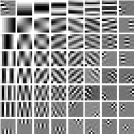

First, we study transform training based on Mayo Clinic data. As shown in Fig. 6, seven slices obtained at regular dose from three patients are used for transform learning. The number of pixels . Similar to the phantom experiments, overlapping patches are extracted with a patch stride. The number of overall training patches is about . We set for ST, , , for MARS2, , , , , for MARS3, , , , , , , , , for MARS5, , , , , , , , , , , , , for MARS7. The iteration number in Algorithm 1. Fig. 7 illustrates the learned transforms obtained with Mayo Clinic data. Different from the XCAT phantom case, these transforms up to MARS5 display more complex features and structures. The rich features of the MARS models better sparsify the training images over layers compared to the single-layer model (ST).